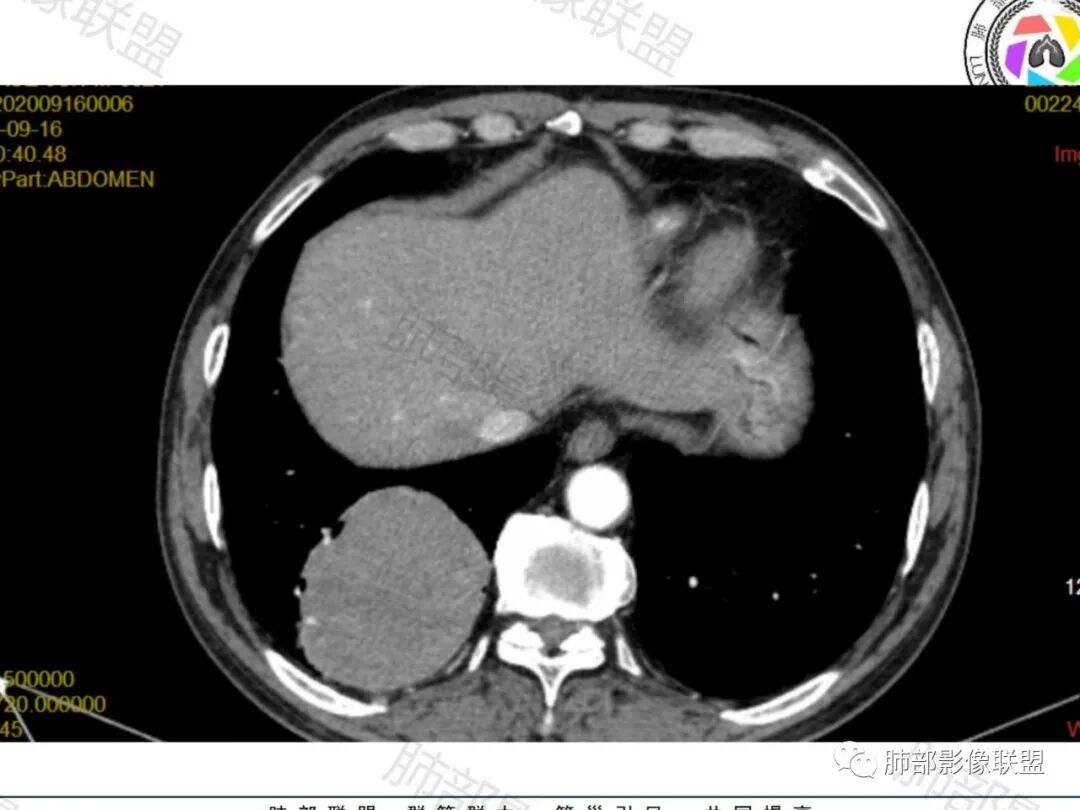

右肺下叶一类圆形肿块影,内缘边缘光滑,外缘边界模糊,可见磨玻璃影,整体以彭隆为主,部分边缘包绕支气管,平扫密度尚均匀,增强后不均匀强化,部分与膈肌黏连,临床,62岁男性,无症状,考虑恶性:腺癌,鳞癌,神经内分泌癌,肉瘤

男性,62,胆结石入院胸部CT偶然发现占位。肿标稍增高,右肺下叶胸膜下肿块,边缘尚清,密度较均匀,增强明显强化,血管贴边,空气新月征?静脉期可见低强化区,首先考虑PSP,鉴别肉瘤样癌及神经内分泌肿瘤

老年男性,肿瘤标志物高,右肺下叶类圆形肿块,宽基底与胸膜相连,边缘光整,密度均匀,周围气管及血管受压推移,延迟强化,其内见纤细血管,似有小低密度灶,首先考虑间叶组织恶性肿瘤,良性平滑肌瘤、纤维瘤不除外

患者中老年男性,检查发现右下肺占位。查肺癌标记物稍有升高。血常规白细胞计数稍降低。胸部CT:右肺下叶后基底段类圆形肿块,边缘光滑,边界清楚,周边见气管受压扩张,增强轻度强化,内见点状低密度影,见血管贴边。综合考虑良性过低度恶性病变,PSP可能,其它恶性肿瘤待排。

老年男性,检查发现右下肺占位。CT:右肺下叶一类圆形肿块影,膨隆,无分叶,边缘基本光滑,近端支气管推挤狭窄,与胸膜夹角为锐角,增强见不均匀强化,未见坏死,近端见血管贴边,胸壁脂肪间隙清楚。考虑良性病变——PSP可能性大。鉴别神经内分泌癌、肉瘤、SFT。

右肺下叶软组织肿块,边缘光滑,临近血管受压变形且增粗,增强后见斑片状低强化区,界不清,实性部分见条状血管影,边缘光滑,考虑PSP可能,肿块与支气管关系不密切,腺癌,腺鳞癌不符合,肿块内增强后血管走形自然,间叶组织起源肉瘤不符

右肺下叶肿块,呈外带大内带小的椭圆形改变(内带受支气管及血管挤压原因),边缘光滑,无分叶毛刺,支气管受压,增强后,均匀延迟强化,动脉期见血管贴边,静脉期内部瘤样血管强化区,相邻胸膜无侵犯,纵隔无淋巴结肿大,符合PSP,不鉴别。

胸部CT:右肺下叶一类圆形肿块影,边界清楚,大部分边缘光滑、外缘边界模糊,邻近支气管推移、血管贴边,病灶内可见分枝状血管,平扫密度尚均匀,增强后大部分均匀延迟强化,部分与膈肌黏连、尾征?考虑:类Ca>PSP>SFT。鉴别肉瘤样Ca,CD等。

肿块位于周围(起自细支气管呼吸道上皮),均匀膨胀生长(符合良性的生长特点),病灶内部大部分密度较均匀,部分小低密度不强化区(囊变),增强强化较明显,边缘血管增粗贴边,临近支气管受压,支持PSP。

常规肿瘤如果背侧胸膜来源,肿瘤与胸膜之间不应该夹杂含气支气管,会推移

但是肺内可以将支气管外推,夹在胸膜之间

与膈面胸膜类似推断

支持肺内

但是这条血管需要交代一下:

如果这是同一根肺动脉,支持PSP

因为肺门区来源肺动脉